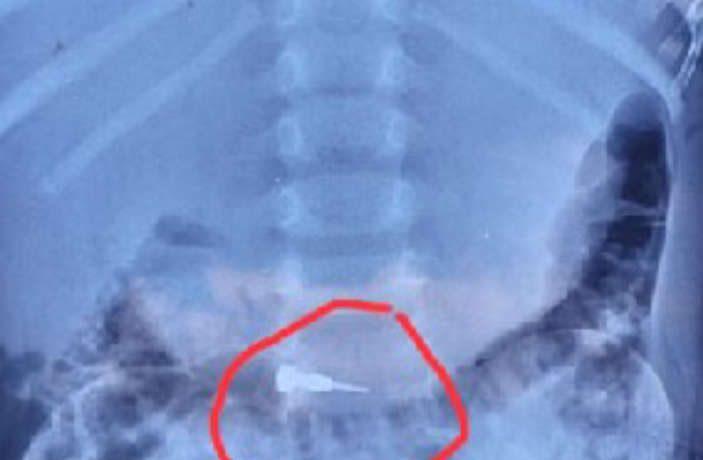

അയാൻ അവശനിലയിൽ ആയതോടെ ആശുപത്രിയിൽ കൊണ്ടുപോകണമെന്ന് ആവശ്യപ്പെട്ടപ്പോൾ ഡോക്ടർ എക്സ് റേ എടുക്കാൻ എഴുതി നൽകി. പടിഞ്ഞാറത്തറയിലെ സ്വകാര്യ ആശുപത്രിയിൽ നിന്നുള്ള എക്സ് റേയിൽ കുട്ടിയുടെ വയറ്റിൽ സിറിഞ്ചിനോട് സാമ്യമുള്ള ഉപകരണം കണ്ടെത്തുകയും മെഡിക്കൽ കോളജിലേക്ക് റഫർ ചെയ്യുകയുമായിരുന്നു. ഈ വിവരങ്ങൾ ധരിപ്പിക്കാനായി ക്ളിനിക്കിലെത്തിയപ്പോൾ ഡോക്ടർ ദേഷ്യപ്പെടുകയും കൈയേറ്റം ചെയ്യുകയും ചെയ്തതായി അയാന്റെ പിതാവ് അബ്ബാസ് പറഞ്ഞു.

മാനന്തവാടി മെഡിക്കൽ കോളജിലെ സ്കാനിങ്ങിലും വയറ്റിൽ ഉപകരണം കണ്ടെത്തി. ഇതോടെ കുടുംബം കുട്ടിയുമായി മേപ്പാടിയിലെ സ്വകാര്യ ആശുപത്രിയിൽ ചികിത്സ തേടി. രണ്ട് ദിവസം കാത്തശേഷം കുട്ടിക്ക് സർജറി വേണമോ എന്ന് തീരുമാനിക്കാമെന്നാണ് ഡോക്ടർമാർ അറിയിച്ചത്. അതേസമയം, ചികിത്സക്കിടെ ഉപകരണം വായിലേക്ക് വീണപ്പോൾ പുറത്തെക്കെടുക്കാൻ ശ്രമിക്കുന്നതിനിടെ മാതാവ് കുട്ടിയെ ശക്തിയായി കുലുക്കിയതോടെയാണ് ഇത് ശരീരത്തിലേക്ക് പോയതെന്ന് ഡോക്ടർ പറഞ്ഞു. തുടർ ചികിത്സക്കുള്ള സൗകര്യം ഒരുക്കിയിരുന്നതായും ക്ളിനിക്ക് ഉടമ ഡോ. ഹാഷിം അറിയിച്ചു.